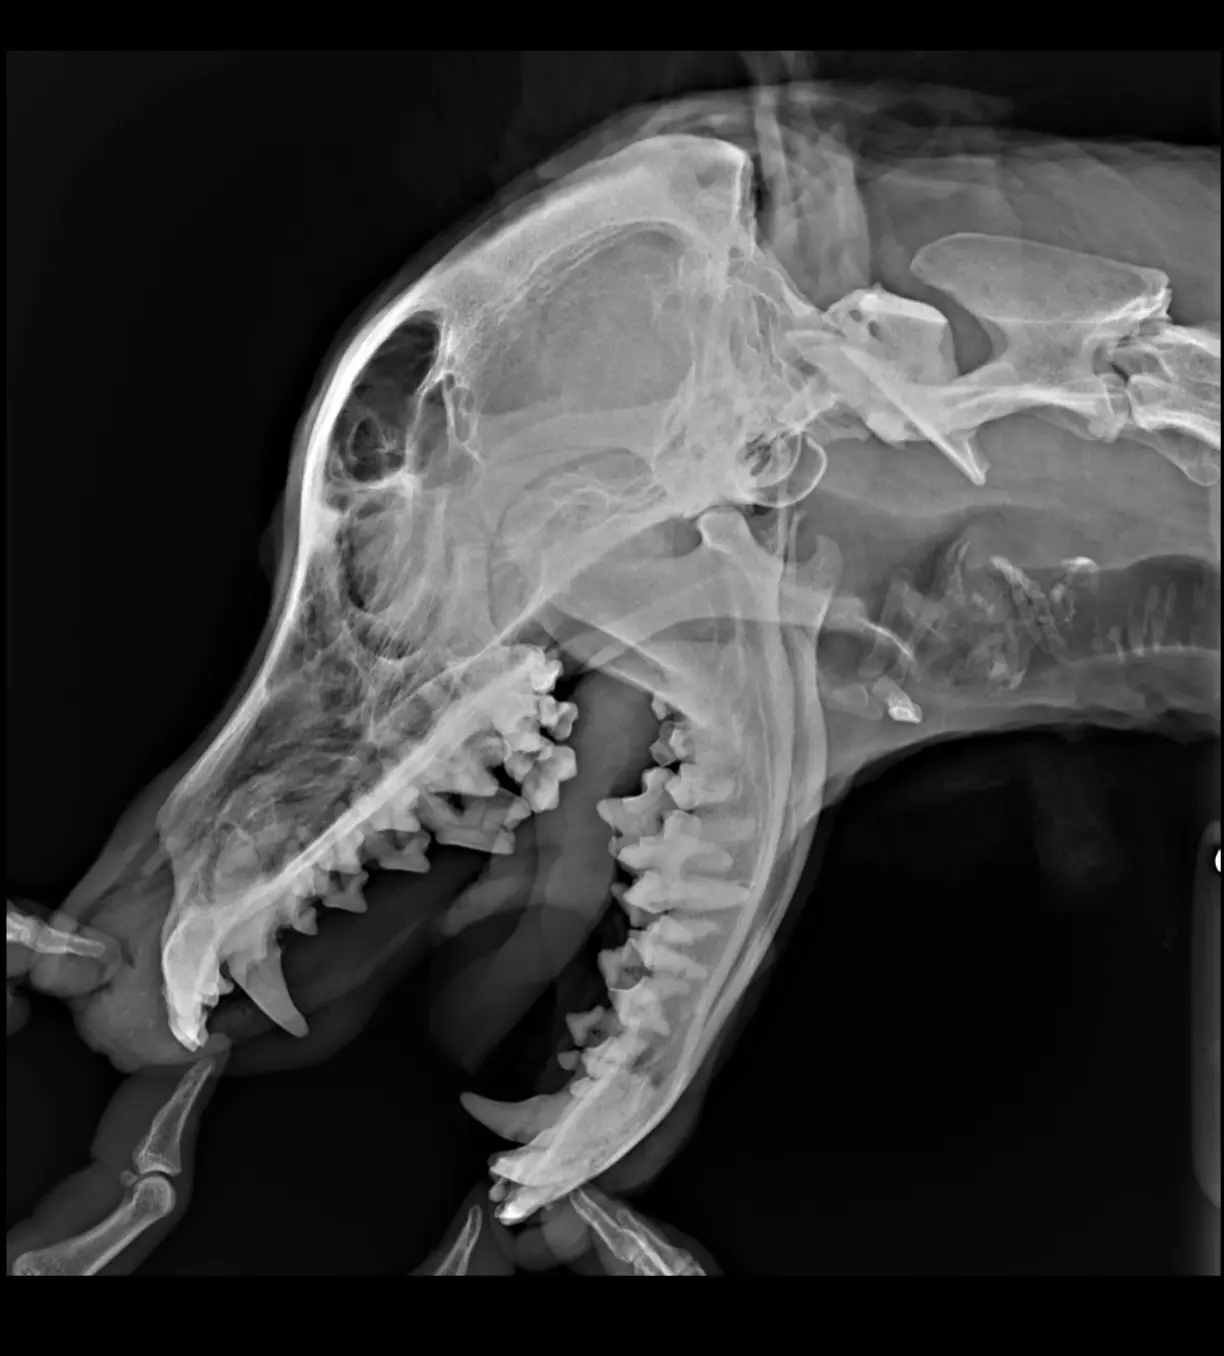

06.03 - посещение хирурга-стоматолога.

Результаты посещения ошеломляюще плохие:

2. Дырка от клыка не заросла . Проход широкий, сквозной.

5. рентген челюсти.

Зашивать дырку. Если сопли не уйдут, тогда делать КТ. Сейчас смысла нет.